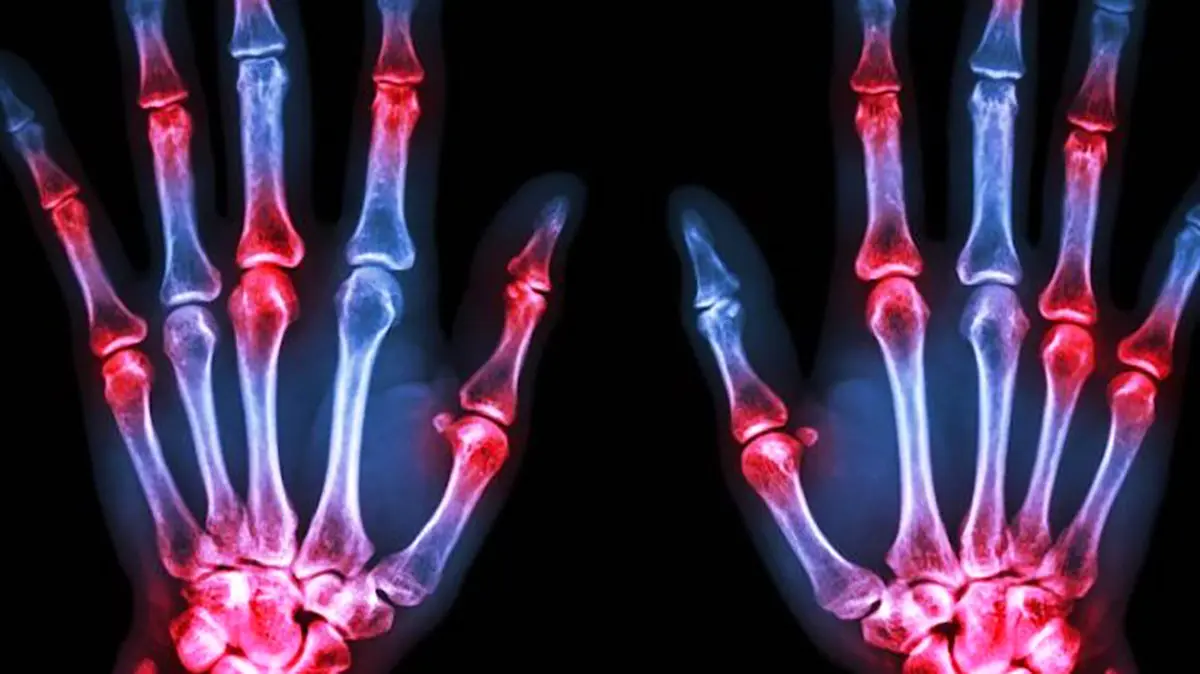

آرتریت روماتوئید (Rheumatoid Arthritis):

یک بیماری خودایمنی است که باعث التهاب مزمن در مفاصل میشود. این بیماری میتواند به تخریب مفاصل و کاهش دامنه حرکت آنها منجر شود.